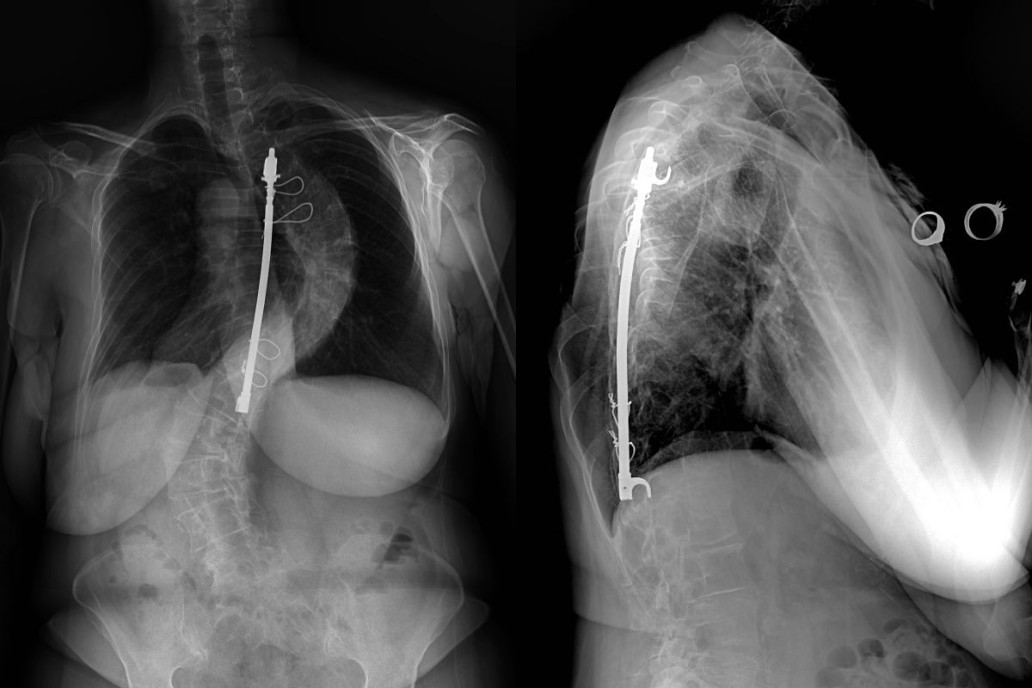

From www.sciencephoto.com

Thoracic Harrington Rods on Chest XRay Stock Image C043/0306 Are Harrington Rods Mri Compatible the only issue is that the images will be a little blurry directly around the hardware, especially if it is stainless. learn about the mr safety and artifacts of orthopedic implants made of different metals, including titanium. Patrick, many of the modern rods and plates are now made of titanium that should not be responsive to. the. Are Harrington Rods Mri Compatible.

Thoracic Harrington Rods on Chest XRay Stock Image C043/0305 Are Harrington Rods Mri Compatible Browse the list by object. Find out how to scan patients with total joints. the compatibility of various orthopedic implants with magnetic resonance imaging (mri) has been. learn about the relative contraindications of mri for patients with spinal fixation hardware, including harrington rods. find out the safety status of various orthopedic implants, materials, and devices for mri. Are Harrington Rods Mri Compatible.